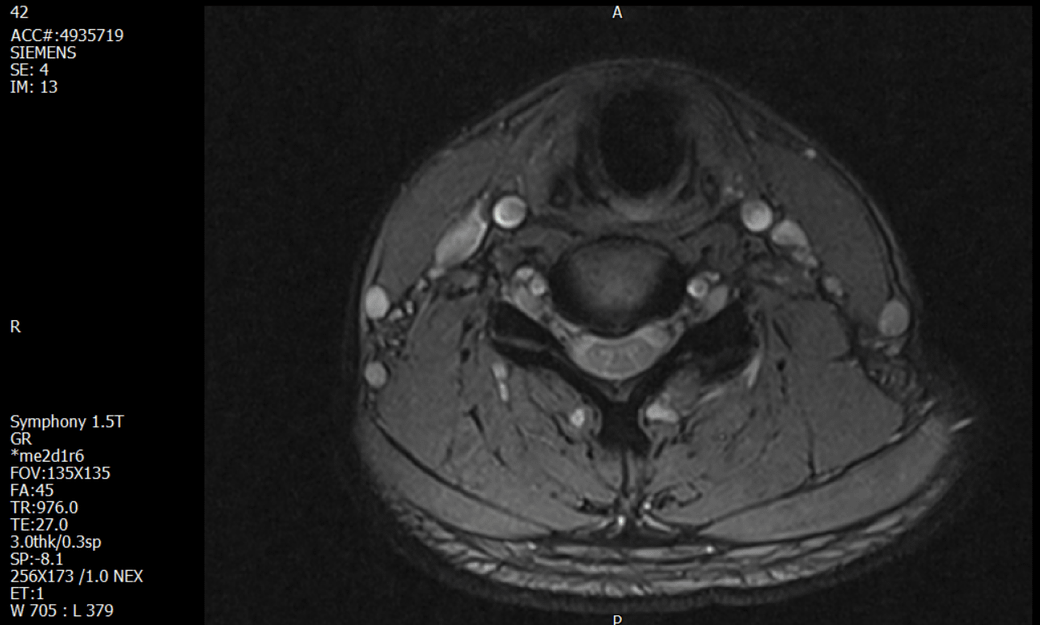

경추 요추 디스크 MRI판독 부탁드립니다.

- 3개월전 좌측 상지 저림(힘빠짐) 발생. 이틀뒤 에 좌측 하지 저림(힘빠짐) 발생.

(힘이 축처지는 느낌이라서 힘빠짐이라고 하지만, 실제 근력 문제, 감각이상, 활동 문제 없음)

1. MRI 상 , 경추와 요추에 디스크가 있나요? 있다면 좌측 팔과 다리에 저림 및 힘빠짐을 줄 정도인가요?

특히나 요추MRI는 문제가 없다고 들었던 터라 다리저림은 어떻게 설명할수있는것인지 모르겠네요.

• 3번 째 사진

• 1. MRI 사진을 보았을 때 디스크를 의심해볼 수 있는 소견이 살짝살짝 보이긴 합니다만, 상하지의 저림 및 힘빠짐을 유발할 정도인지는 솔직히 회의적입니다.

3. 개인적으로는 디스크로 인한 증상이 아닐 것으로 보나, 만약 디스크가 맞다면 우연하게 목과 허리 디스크 발병이 이틀 간격을 두고 나타났을 가능성을 생각해야 하는데, 현실적으로 그 가능성이 높지 않습니다.

4. 말씀하신 것처럼 특히 요추부 MRI는 디스크를 찾기 어렵습니다.

상기 MRI 소견으로는 심한 증상을 보일 정도는 아니며 디스크의 가능성은 적어보입니다.